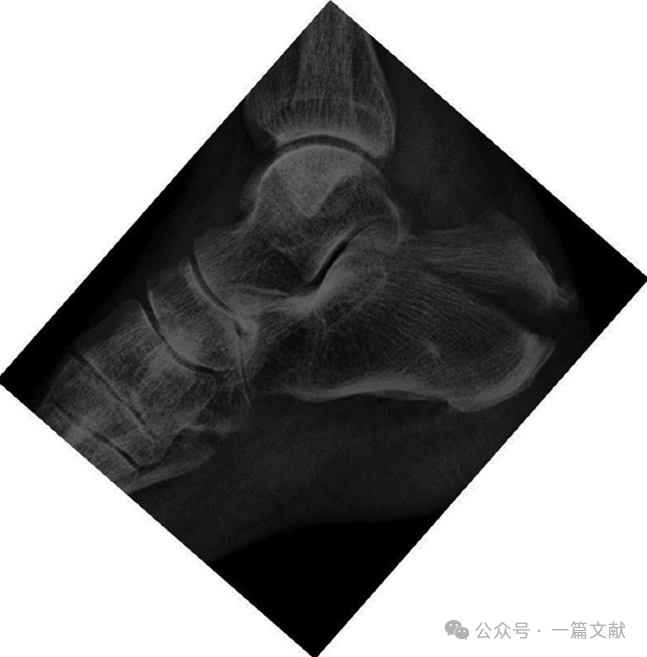

3.2跟骨轴位片:

常用于观察(1)主骨折线,(2)跟骨结节的外翻移位,(3)跟骨宽度;以及(4)后距关节面的损伤,如下图: